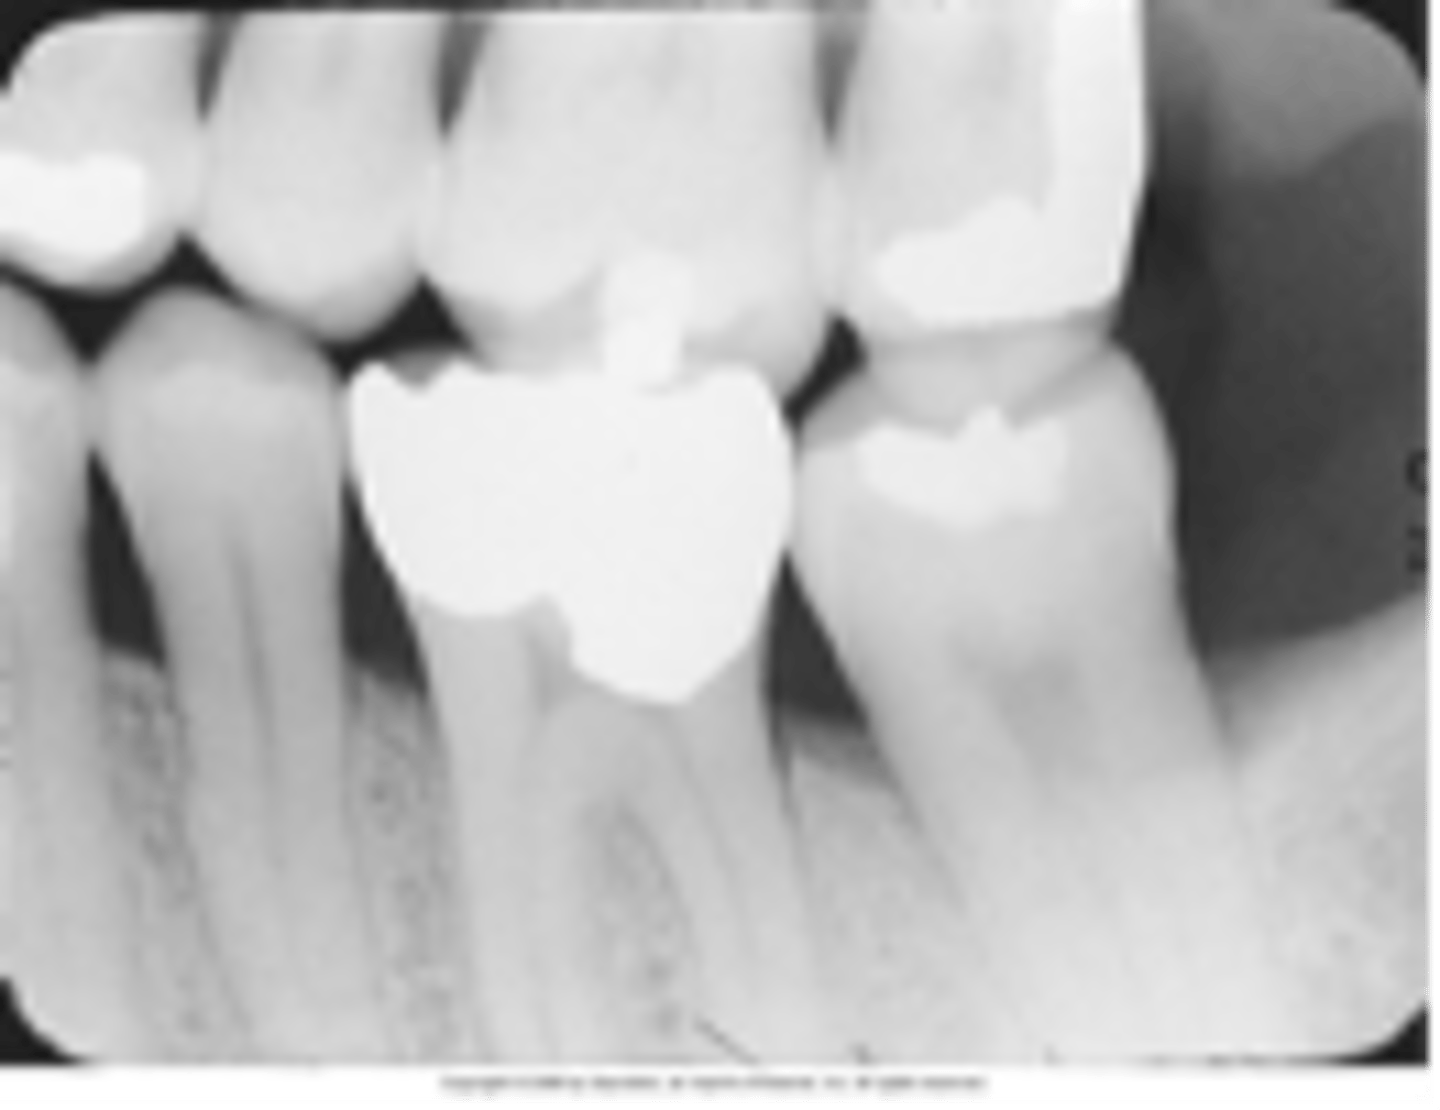

MOD amalgam

overhang

PINS